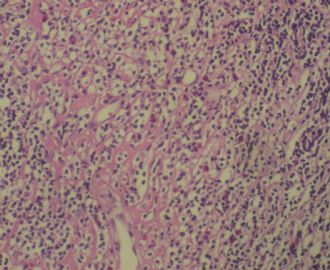

姓    名: ××× 性别:  女 年龄:  77岁

标本名称:  左前臂数个大小不等的皮下肿物。

既往有非何杰金淋巴瘤(滤泡性淋巴瘤)病史22个月。

病例不错。细胞胞浆透亮,间质血管丰富,图片不是很清晰,似乎有嗜酸粒细胞?

恶性,首先考虑T-NHL。IHC证实。

既往有NHL病史,图片不太清晰,细胞弥漫,胞浆透亮,首先考虑T细胞淋巴瘤。

上华夏网不久,在软组织中跟了几个帖子,本例有非何杰金淋巴瘤(滤泡性淋巴瘤)的病史, 不知治疗情况如何,若治疗后,其形态学来区分T,B不可靠,看免疫组化结果. 最好把前次的图片也上传,以便对照